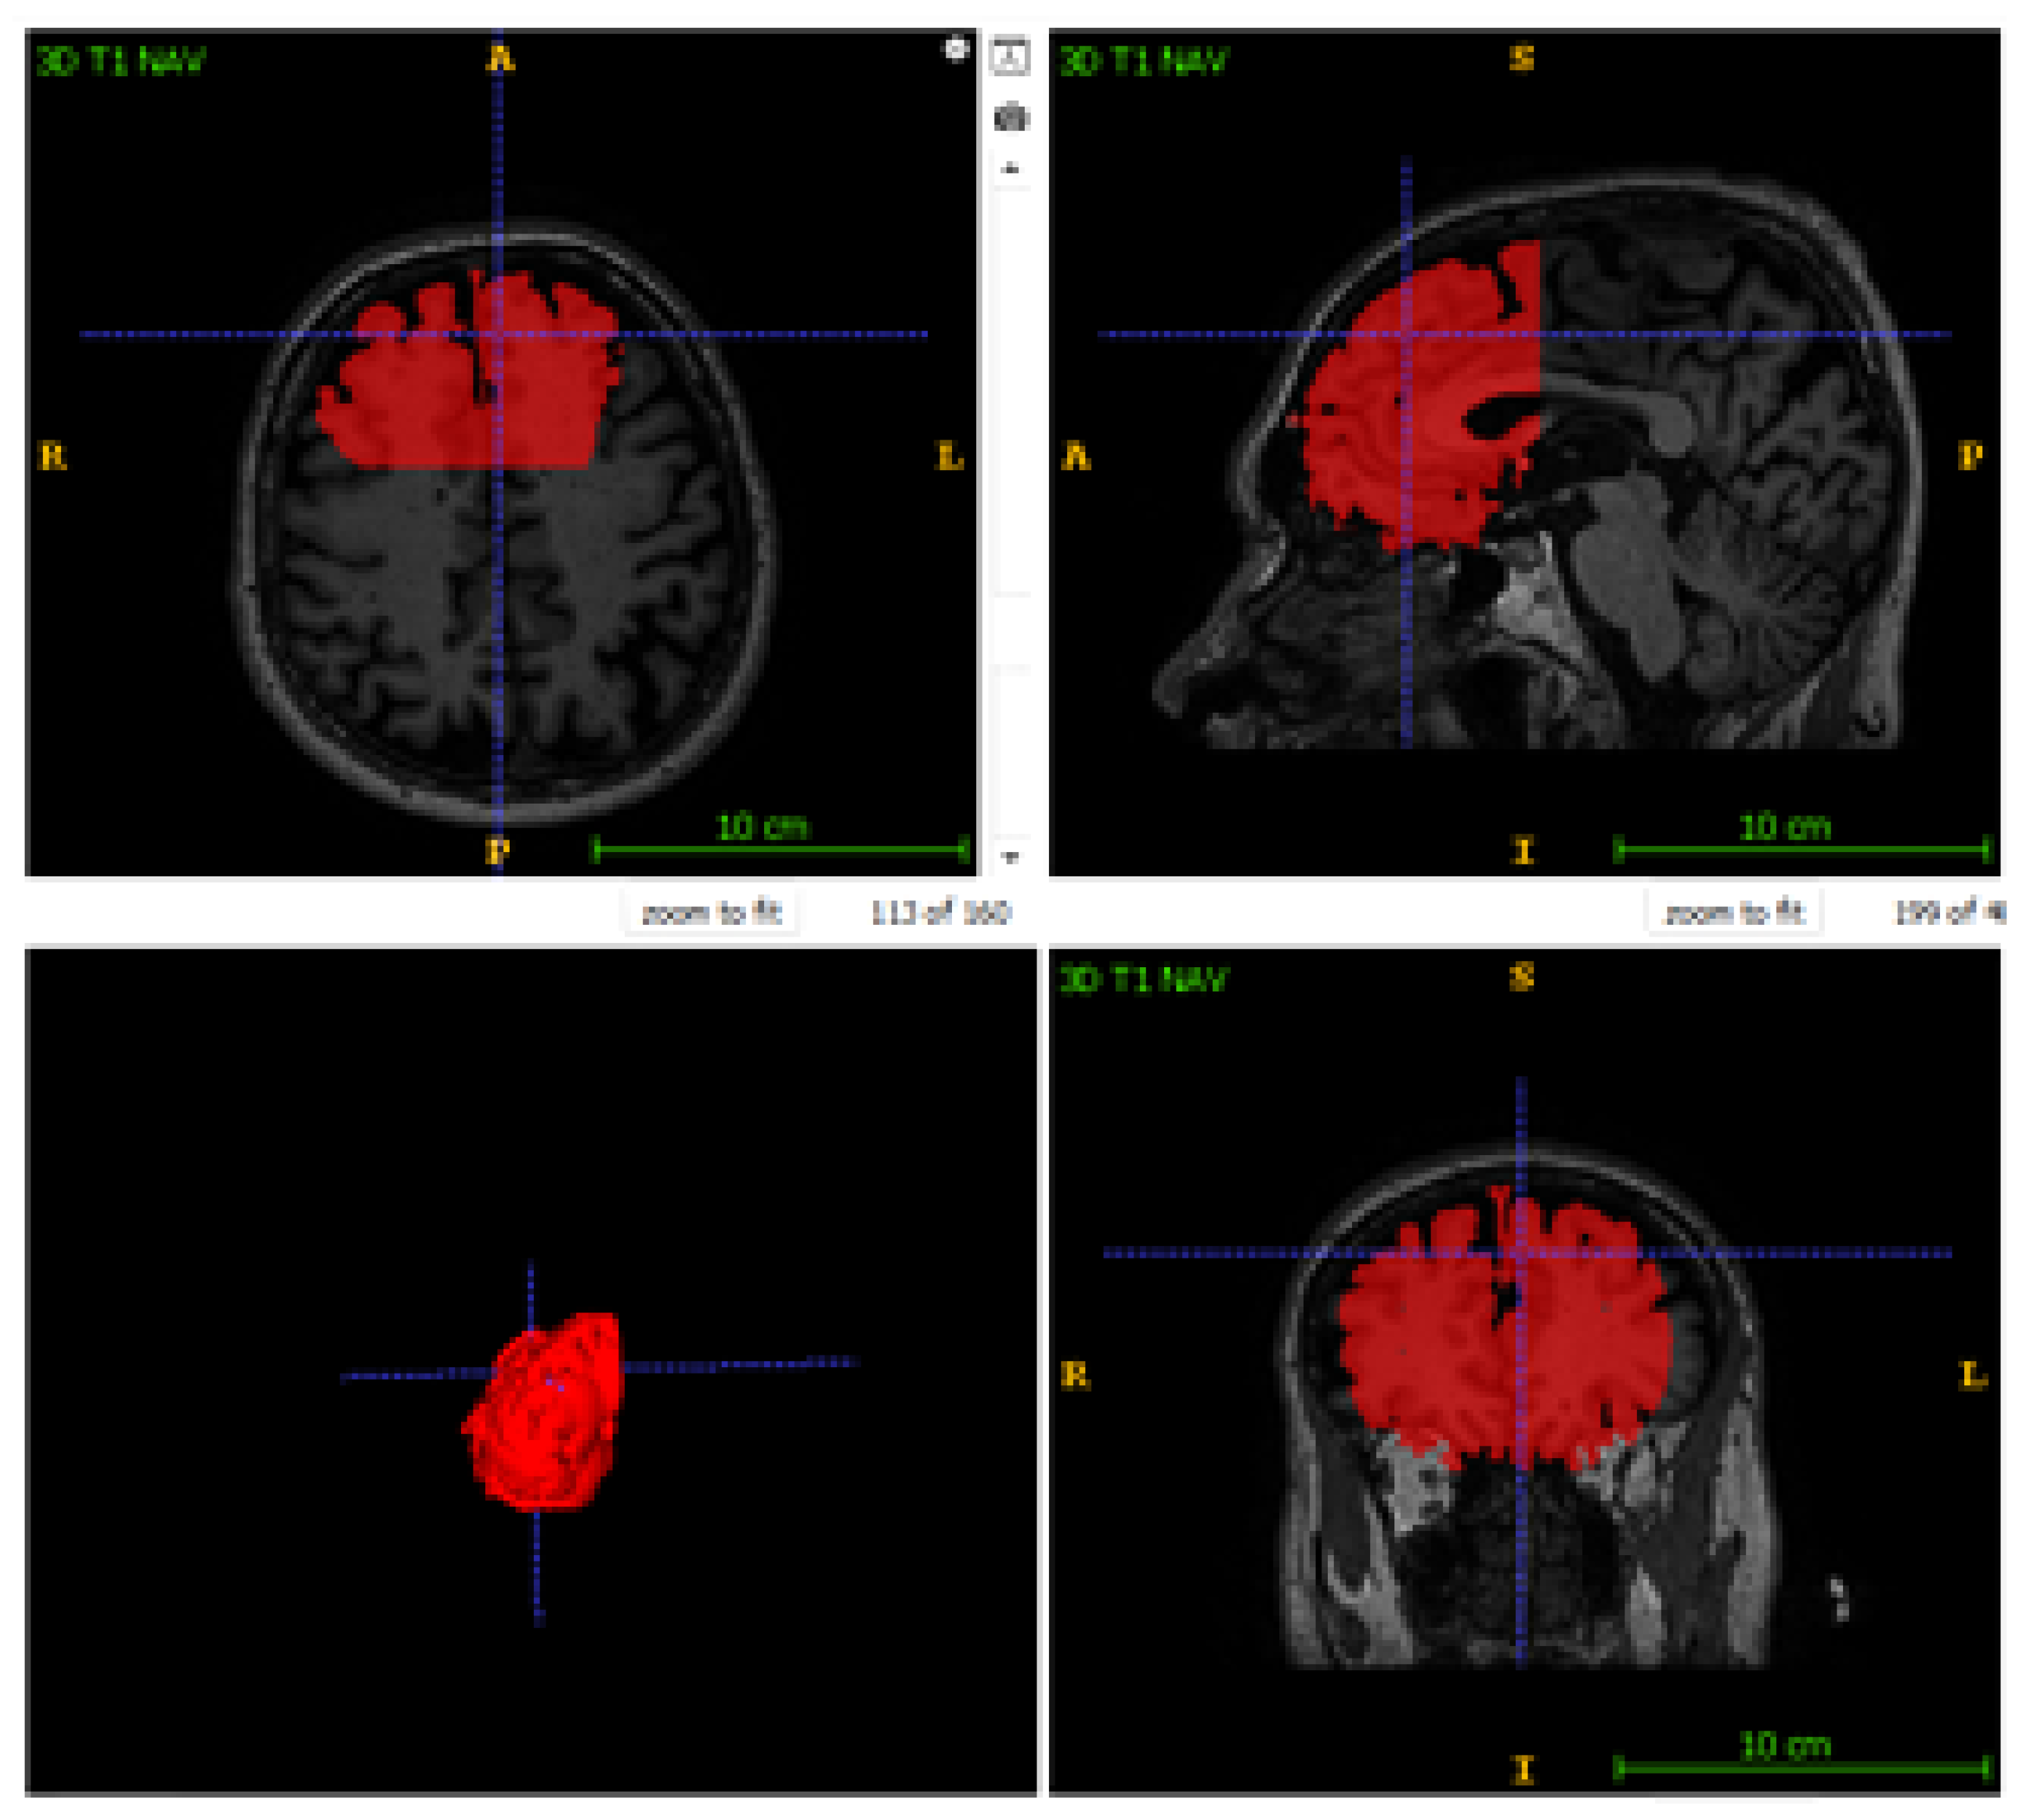

Quantitative metrics alone do not fully capture clinical usability. Visual inspection of three-dimensional reconstructions provides complementary insight into anatomical plausibility and localization accuracy, as shown in Figure 6.

Across all cases, including those with lower DSC values, the model correctly localized the centroid of the Middle Frontal Gyrus, demonstrating robust spatial targeting. Predicted segmentations adhered to sulcal boundaries without spillover into adjacent gyri, indicating that the network learned meaningful topological constraints rather than relying solely on local texture cues.

Figure 6. Qualitative Segmentation Results. Left: Accurate localization in Case 3. Right: Under-segmentation in Case 2 caused by interrupted sulcal patterns absent from the training data. (a) Case 3: Precise MFG localization (b) Case 2: Under-segmentation due to atypical gyrification.